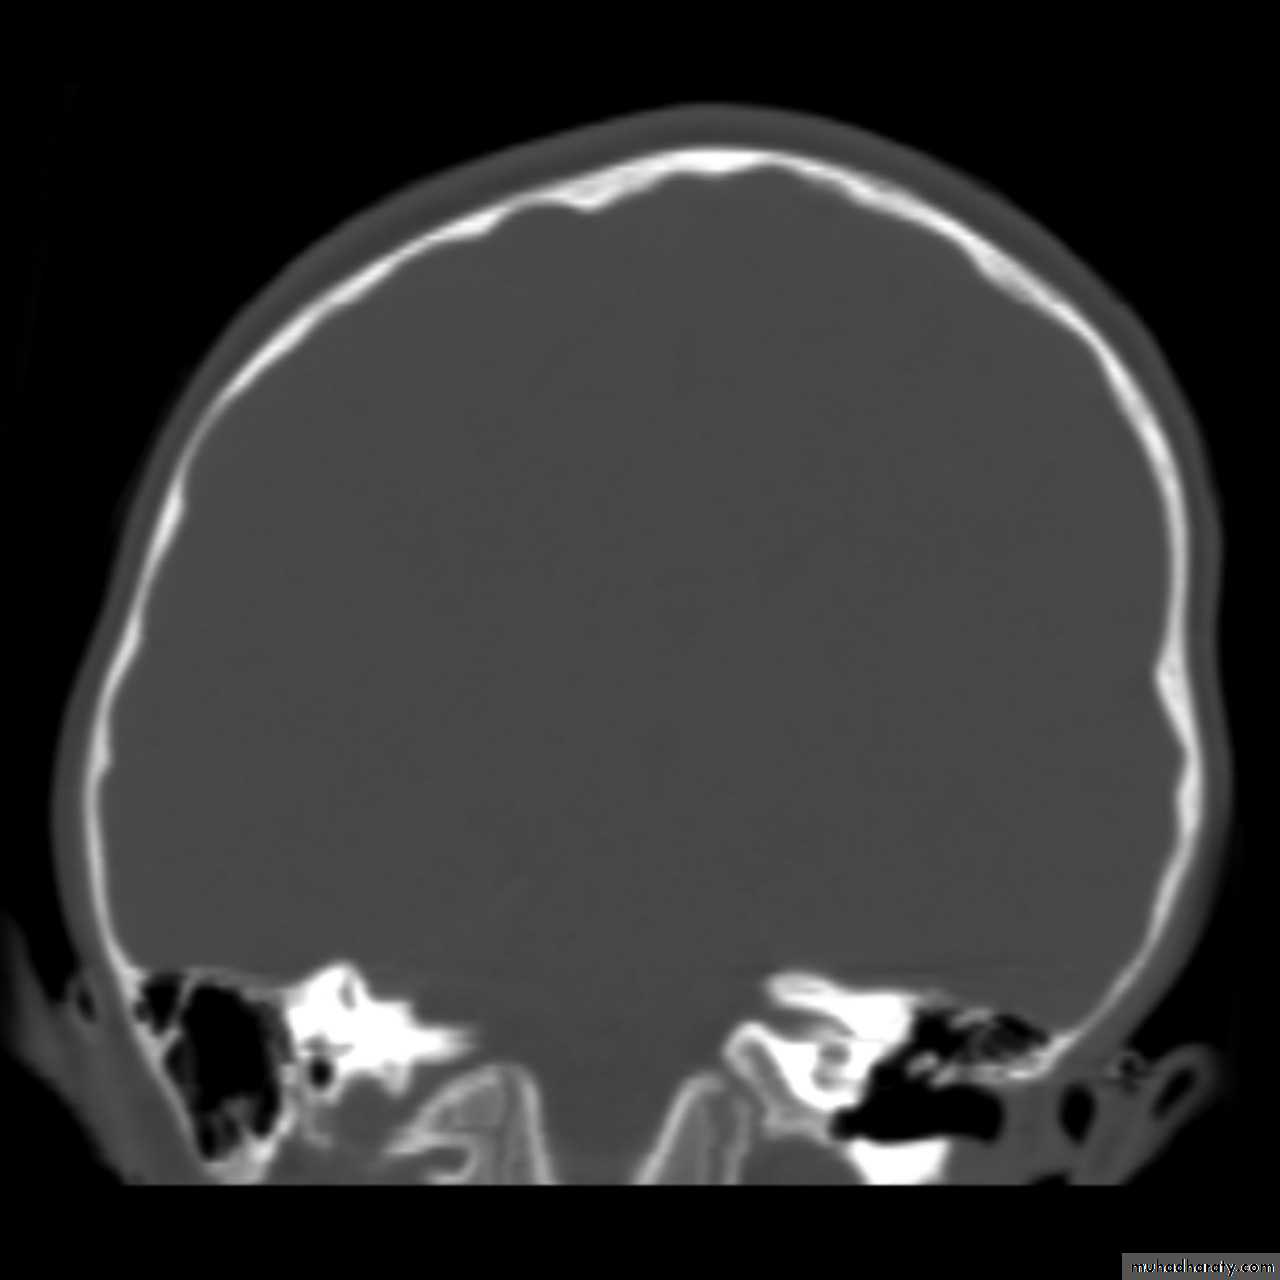

Skull X-ray findings in increased intracranial pressure

• Sutural separation in children.• ‘Copper-beating’ marking of the cranial vault.

• Thinning of dorsum sellae.

• Erosion of the posterior clinoid process.

Copper-beating’ marking